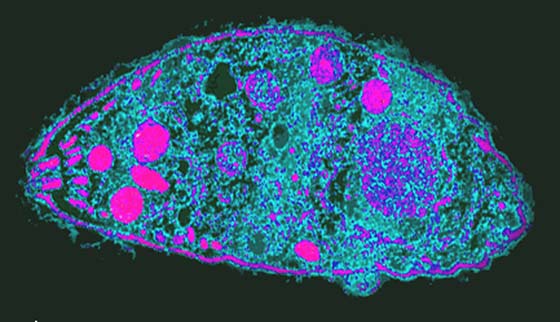

image

Toxoplasma под микроскопом